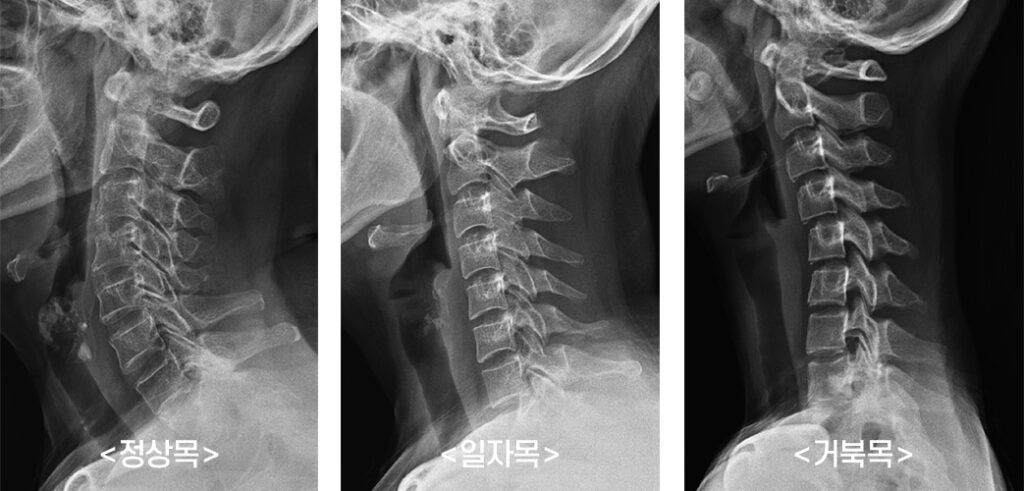

목디스크 환자 중에 목디스크 증상으로 느끼게 될수 있다고 하며 두통의 경우 목에서 뇌로 높게 되는 혈관 또는 신경이 압박되어 원만한 순환이 되지 않으니 생겨날 수 있고 환자분들께서 체감할 수 있는 어지럼증, 이명, 어지럼증, 현기증, 두통입니다. 그리고 목과 맞닿은 경추 신경이 자극을 받아 발생하는 증상으로 해로운 자세로 수세기 스마트폰을 본다거나, 책을 읽은 것, 컴퓨터사용을 하여 거북목 증상이 일어나는 되었다면 빈번히 발생할 수 있어요.